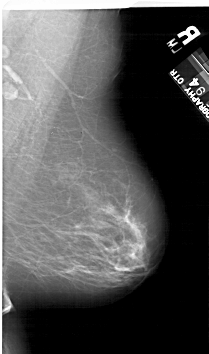

A_1124_1.RIGHT_MLO

RIGHT_MLO LINES 6361 PIXELS_PER_LINE 3751 BITS_PER_PIXEL 12 RESOLUTION 43.5 NON_OVERLAY